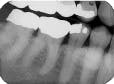

The bisecting-angle technique creates specific errors in vertical angulation, giving shortened images (see Radiograph 2 as an example of foreshortening) or lengthened images (see Radiograph 3 as an example of elongation). Substantially shortened images occur because there is too much vertical angulation. This causes distortion in the reproduction of the actual size of the tooth. The solution requires a decrease of the vertical angulation by at least 10 degrees.

Conversely, lengthened im-ages occur because there is not enough vertical angulation. Another reason is that the film is curved in the mouth. Increasing the vertical angulation by at least 10 degrees and repositioning the film to prevent bending will alleviate this distorted image.